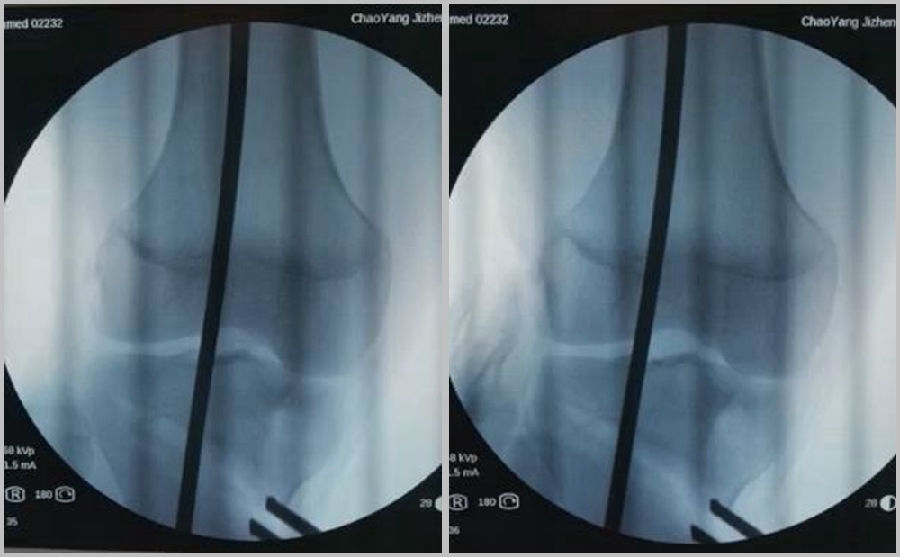

一、合页骨折

合页骨折分为3型:Ⅰ型,骨折是截骨线的延伸,位于上胫腓关节近段或刚好位于上胫腓关节;Ⅱ型,骨折延伸到上胫腓关节的远端;Ⅲ型截骨线通向外侧胫骨平台,也可以称为胫骨外侧平台骨折。

合页骨折分型

1、原因及预防

(1)合页位置

合页的位置应放置在腓骨头尖,距离外侧平台1.5cm处。这个位置不单是骨性合页,同时也有很强的变形能力,很强的弹性,而且它周围有较多软组织合页,比如上胫腓关节、髂胫束、外侧关节囊等。

a.合理;b.过低(Ⅱ型);c.过高(Ⅰ型)

(2)合页宽度

合页具有一定的变形能力,同时还有一定的强度,一般要保留1cm左右的宽度。如果合页保留过宽,那么此时合页强度过强,而变形能力不够,在过度撑开时会出现骨折,易造成Ⅲ型骨折。如果合页保留过窄,就会容易截过了,容易出现Ⅰ型骨折。所以强调合页宽度要求要在1cm左右,这样才具有一定的稳定性,同时还有一定的变形能力。

a.合理;b.过宽(Ⅲ型);c.过窄(Ⅰ型)

(3)拉力钉技术

第3个原因和拉力钉使用技术有关。拉力螺钉的使用是希望在合页端产生一个加压的效果,如果拉力螺钉使用过度,会出现合页端拉断的情况,导致Ⅱ型骨折。所以要求拉力螺钉在使用时加压不要过度,通常当钢板有轻微的变形即可,不要过度加压。